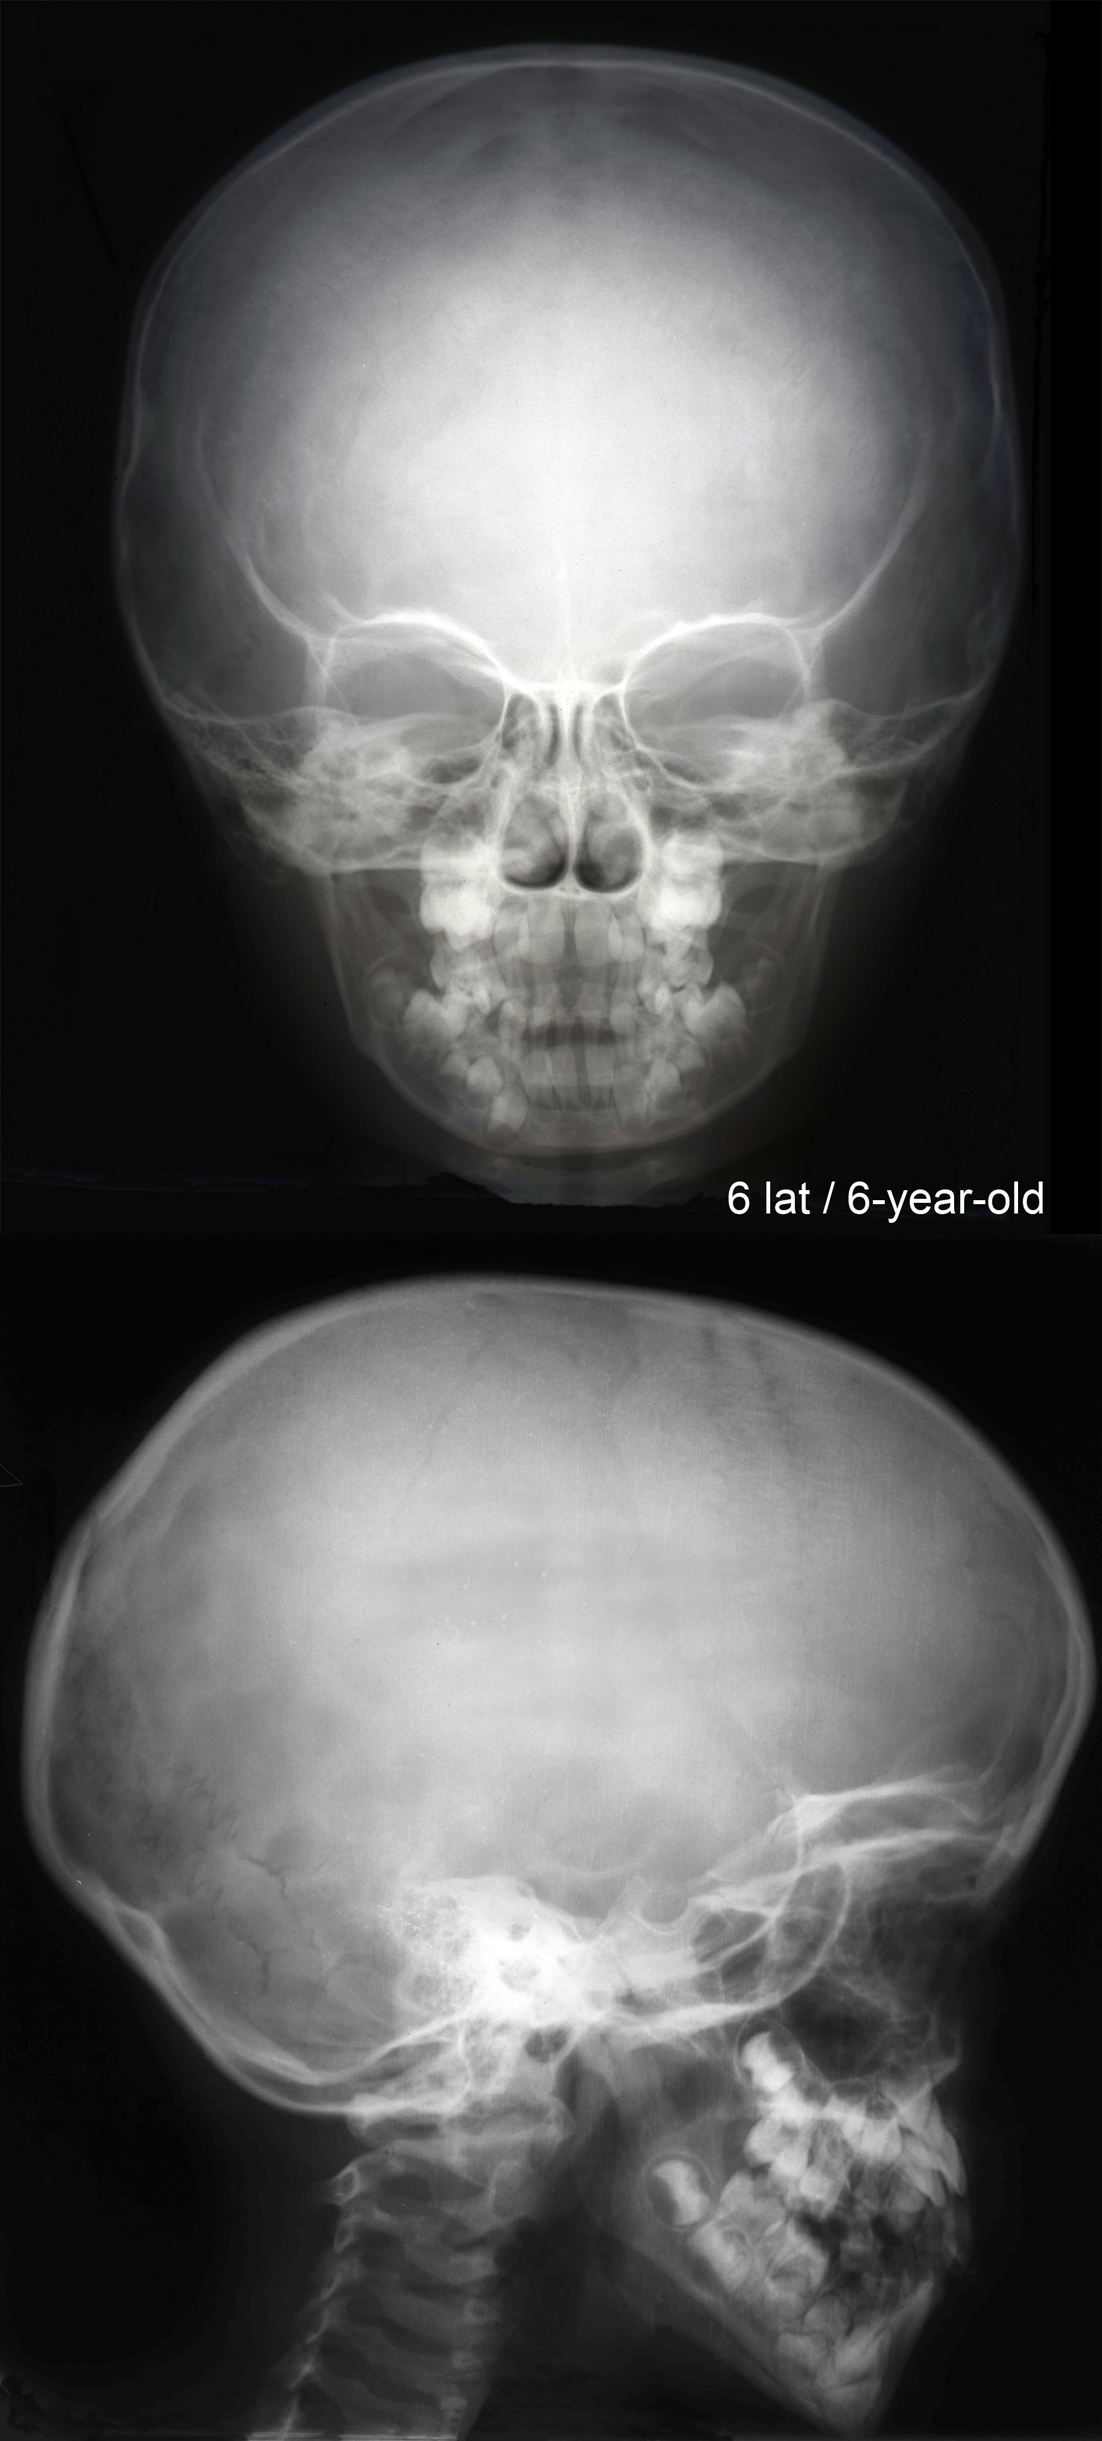

RTG głowy 6-letniego dziecka..

RTG głowy frontalny.

RTG głowy boczny.